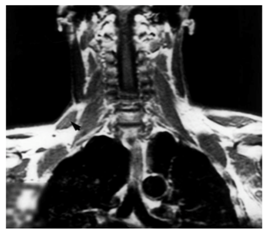

Hug et al.14 also reported a rare anatomical presentation. In a 48-year-old patient with chronic pain and deformities of the right upper limb, they found an accessory portion of the trapezius muscle. This accessory portion crossed the upper part of the brachial plexus, explaining the symptoms on the upper limb. Excision of the anomalous muscle and release of the clavicular part of the sternocleidomastoid muscle abolished the complaints (Figure 3).

Figure 4 A: Swelling (arrow) in the right posterior triangle of the neck.

B: Frontal magnetic resonance section showing the accessory part of the right trapezius muscle (arrowhead).14